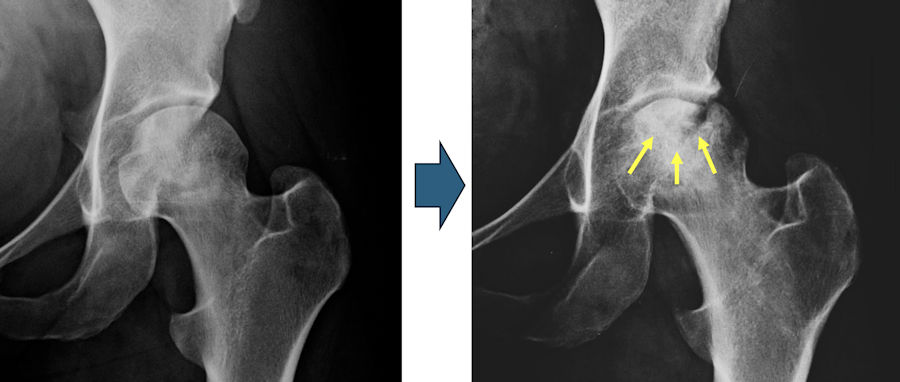

Femur başı avasküler nekrozu tanısında dikkatli bir muayene sonrası röntgen grafileri ve manyetik rezonans görüntüleme (MRG) ile tanı ve evreleme yapılır. Hastalığın ilerlemesi konusunda belirleyici olduğu için kullandığınız ilaçlar, alkol ve sigara miktarını mutlaka doktorunuz ile paylaşmanız gerekir. Hastalığın erken dönemlerinde röntgenler normal olabilir ancak aylar içinde femur başında değişiklikler ortaya çıkar. MRG ile hastalığın başlamasından 48 saat sonra tanı konulabilir. Femur başının tutulum miktarı ve femur başında çökme veya şekil bozukluğu olup olmaması hastalığın seyrini belirler ve tedavi planı yapmak için gereklidir. Ayrıca kan hastalıkları, pıhtılaşma bozuklukları ve lipid yüksekliği gibi durumların da araştırılması, tedavi planlamada önemli yer tutar.

Femur başı avasküler nekrozu çoğunlukla ilerleyicidir. Femur başını besleyen damarlarda kan akımının azalmasına bağlı olarak önce ödem ortaya çıkar, sonrasında pasta dilimi şeklinde başın bir bölümü veya tamamını tutan bölgede kemik ölümü meydana gelir. Başın şeklinin bozulmadığı bu durumda hala eklem koruyucu cerrahiler mümkündür. Sonrasında vücudun tamir mekanizmaları devreye girer ve ölü kemik ile canlı kemik arasında bir ayrışma oluşur, bu da femur başında çökme ve deformasyona yol açar. Bu aşamadan sonra femur başını koruyan cerrahilerin başarı olasılığı giderek azalır. Son evrede hem femur başı hem de karşısındaki yuvada (asetabulum) kıkırdak hasarı ortaya çıkar ve kalça protezi gerekir. İki taraflı avasküler nekrozu olan hastalarda başlangıçta bir tarafta hiç bulgu olmayabilir ancak bunların da % 50-70’inde ilerleyen zamanda bulgu ortaya çıkar, bu nedenle yakınması olsun olmasın her iki kalçanın da tedavi edilmesi gerekir. Sigara ve alkol kullanımı, kortizon kullanımının devam etmesi ve orak hücreli anemi varlığında hastalığın ilerleme riski daha yüksektir. Buna karşın SLE hastalığında ilerleme riski daha azdır.